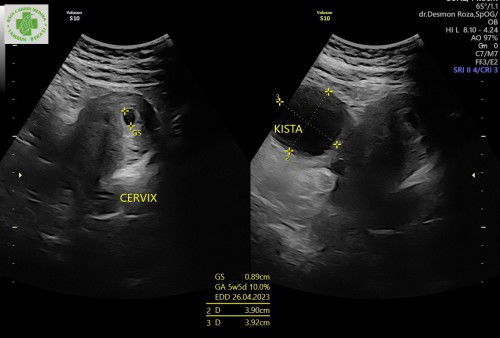

Saya sedang hamil 6 minggu dan ada kista ukuran 3cm. Ini kehamilan pertama saya. Apa ada saran makanan yang baik untuk di konsumsi agar kistanya tidak berkembang? Terimakasih #firstmom

saya juga waktu awal periksa kehamilan ada kista 3.5cm.. dokter spog saya.menyampaikan kista bisa mengecil seiring bertumbuhnya janin, bahkan bisa hilang malahan.. concern ketika ukuran kista semakin membesar diatas 7,5cm.. btw, saya makan apa aja.. dan setelah lahirab Alhamdulillah gak ada lagi kistanya..